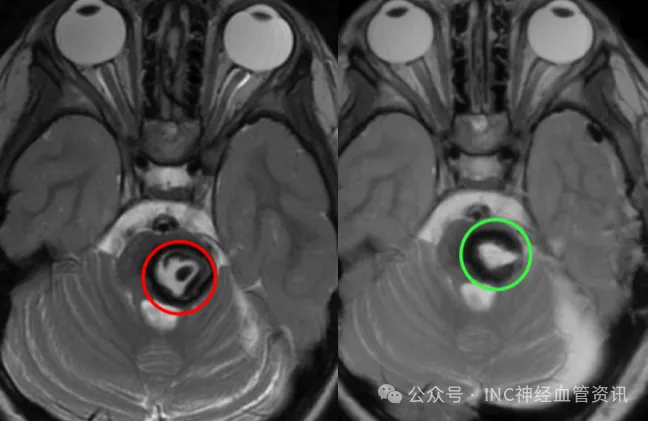

术后第2日拔除气管插管,自主呼吸平稳,CT复查证实病变全切,转至普通病房

术后MRI显示病变完全切除,无脑水肿或出血等并发症,未出现神经功能损伤。除发际线内微小切口外,无其他手术痕迹。